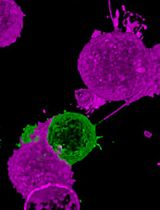

This protocol describes a novel technique to investigate the microcirculation dynamics underlying the pathology in the small intestine of neonatal mice using two-photon laser-scanning microscopy (TPLSM). Recent technological advances in multi-photon microscopy allow intravital analysis of different organs such as the liver, brain and intestine. Despite these advances, live visualization and analysis of the small intestine in neonatal rodents remain technically challenging. We herein provide a detailed description of a novel method to capture high resolution and stable images of the small intestine in neonatal mice as early as postnatal day 0. This imaging technique allows a comprehensive understanding of the development and blood flow dynamics in small intestine microcirculation.

In recent years TPLSM has become increasingly popular in in vivo research. However, intravital imaging of the small intestine in neonatal mice has been challenging due to their small body size and fragility of the intestinal wall. We have developed a novel application of TPLSM to visualize and study the small intestine of neonatal mice in vivo.

Our method allows for direct microvascular blood flow analysis. Stappenbeck TS et al. (2002) reported a method to analyze intestinal microcirculation indirectly from intestinal tissue samples harvested immediately after injecting fluorescein isothiocyanate-labeled dextran into the heart (Yu et al., 2009; Watkins and Besner, 2013; Yazji et al., 2013). However, thisand other similar methods for intravital imaging of the adult mouse intestine are not functional in blood flow dynamics. Our method allows for blood flow dynamics analysis, and facilitates investigation of intestinal villi development and establishment of the capillary network complexity (Stappenbeck et al., 2002). This protocol will allow the investigation of pathological processes associated with intestinal blood flow dynamics in vivo, thus promoting translational research.

The TPLSM imaging method described here can be easily applied to investigate different physiological processes in the neonatal intestine in multiple mouse models. For example, we are using this method to study blood flow dynamics and inflammatory responses in necrotizing enterocolitis (NEC), intestinal epithelium and micro-vasculature development in short bowel syndrome (SBS), inflammatory and immunological status in inflammatory bowel disease (IBD), and ischemia-reperfusion injury in midgut volvulus. Previous studies investigated neonatal intestinal microcirculation in experimental NEC ex vivo, however, these studies did not consider the effects of blood flow dynamics in capillary-vessels in the villi. Our new method allowed us to measure neonatal intestinal microcirculation from movies of live blood flow and to derive blood flow velocity, vessel diameter and inflammation, and assess irrigation of the serosal and mucosal layers. Moreover, this technique is being used to visualize and quantify live blood flow dynamics during reperfusion and ischemia in experimental midgut volvulus, which will be useful to identify the primary intestinal tissues affected.